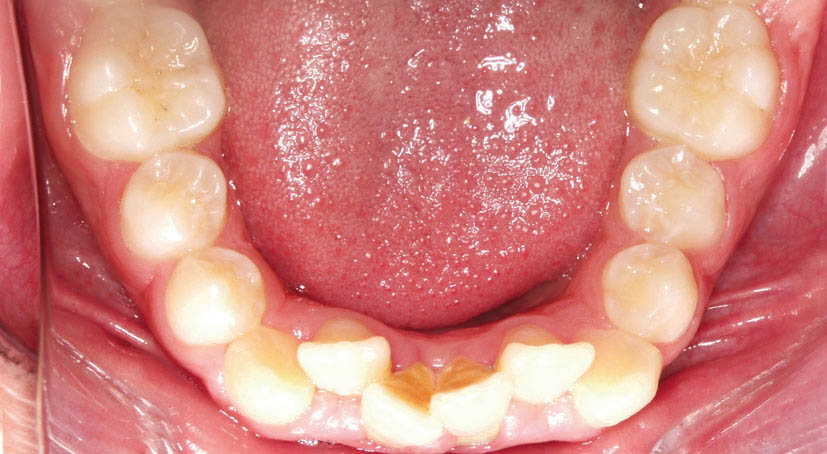

اگر قدامیهای پائین سایز بزرگتری داشته باشند دو حالت رخ میدهد یا پروترود میشوند (شکل 41-2) یا اگر روی همان قوس باشند حالت کرادینگ خواهند داشت (شکل 42-2).

شکل 42-2: انسیزورهای پایین بزرگتر از حد خود هستند اما پروترود نشدند، لذا حالت کرادینگ پیدا کردهاند